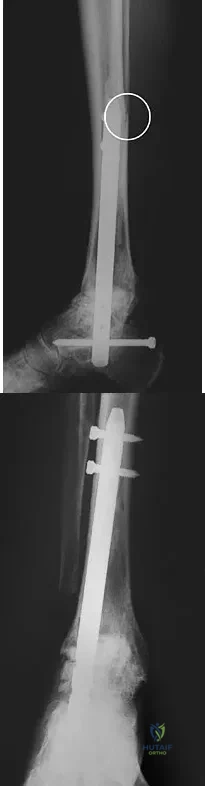

A patient with rheumatoid arthritis with both ankle and subtalar involvement was treated as shown in Figures 11a and 11b. What complication is unique to this type of fixation?

Explanation